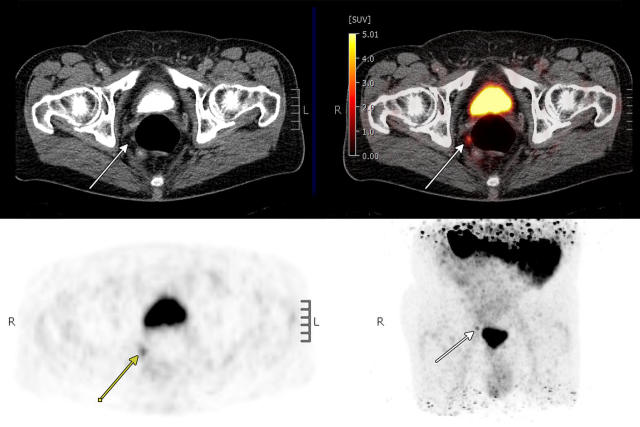

PSMA PT/CT Image

A newer imaging tool, PSMA PET/CT, uses a radioactive tracer that binds to prostate-specific membrane antigen, a protein found on most prostate cancer cells. This allows doctors to detect very small clusters of cancer that would otherwise be invisible on standard scans, making it more sensitive than conventional imaging for detecting prostate cancer recurrence and allowing clinicians to see whether the disease is confined to the prostate bed, has spread to nearby lymph nodes, has traveled to other parts of the body, or is not yet visible. By clearly showing the location and extent of recurrent disease, PSMA PET/CT helps doctors tailor treatment to each patient’s needs. The information can guide personalized decisions, such as whether to expand radiation to the whole pelvis, deliver higher doses to visible tumors, or add hormone therapy.